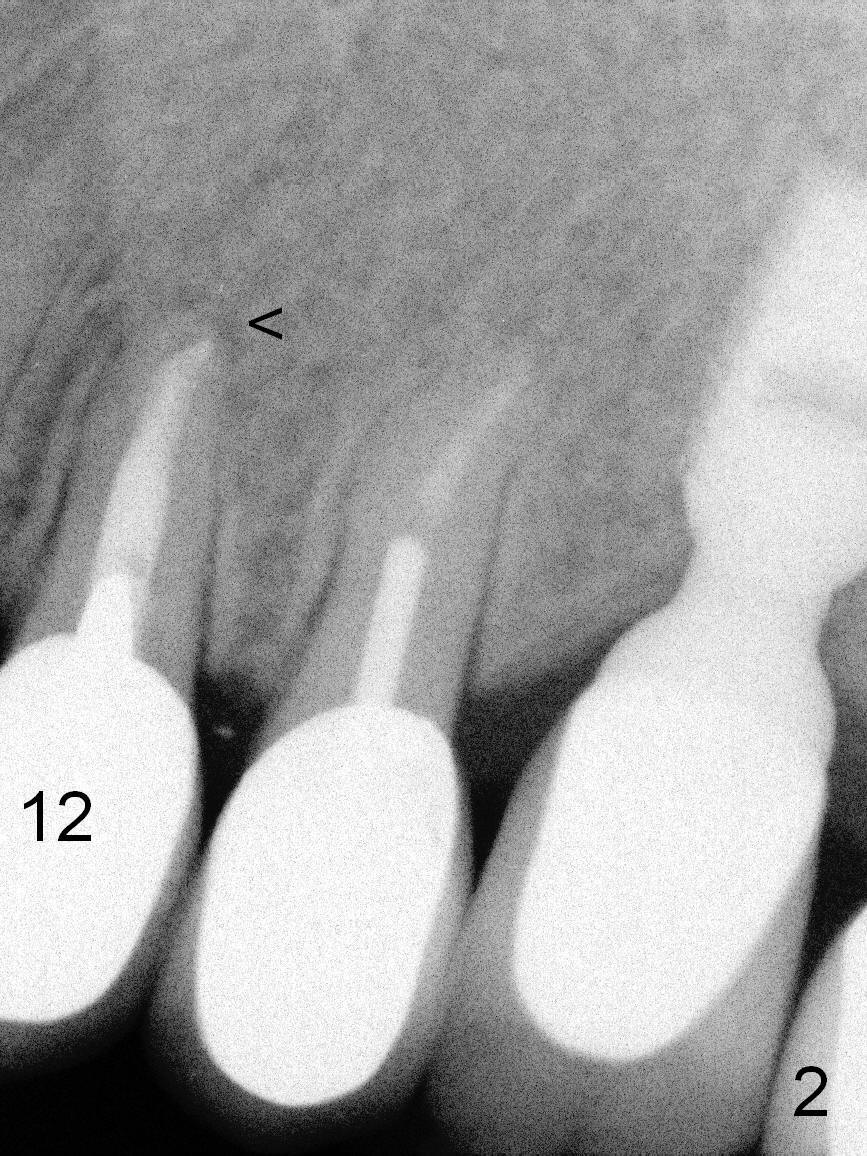

A 57-year-old lady had poor dentition, including periapical radiolucency of the tooth #12, 8 years ago (Fig.1 *, 2007).  After comprehensive treatment, the pathology is apparently under control (Fig.2 <, 2011).  CBCT shows the pathology not completely resolved (Fig.3,4, coronal section, 2012).  Early this year, there was sign of crack tooth at #12 (Fig.5 arrowheads).  Last Saturday she returned because of dislodgement of the crown and post.  The tooth is found to be non salvageable.